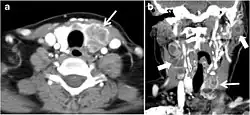

Surgery is the primary mode of treatment for DTCs. Post total thyroidectomy radioactive iodine (RAI) ablation is an option, especially in patients with distant metastasis, tumours larger than 4 cm, or extra-thyroidal disease extension. Ultrasound examination is usually adequate in evaluating primary tumours and cervical lymph nodes. Preoperative cross-sectional imaging with CT or MRI is indicated if there is a concern for local invasion that may alter the patient's staging as well as surgical approach (Figs. 4, 55 and 6)6) . Some thyroid primaries may be small, diffuse, or multifocal and therefore may be occult on imaging (Fig. 4) .[1]

Fig. 4. A 45-year-old male patient presented with anterior mediastinal metastatic PTC lesions and occult primary on imaging. Histopathology examination of the resected thyroid gland revealed micro-foci of PTC; the largest, in the isthmus, measured 4 mm. a transverse greyscale ultrasound of the thyroid demonstrates homogeneous gland with normal echogenicity and size. No focal lesion or micro-calcifications. b Non-enhanced CT scan obtained as part of PET/CT examination shows a heterogeneous, large, relatively dense anterior mediastinal mass (white arrow) with peripheral calcification (arrowheads). Thyroid gland has normal CT appearance with no abnormal FDG uptake (not shown).[1] -

Finally, the possibility of metastatic disease should be excluded. PTCs and medullary thyroid carcinomas tend to metastasize to regional lymph nodes. According to the AJCC/UICC TNM staging system, the nodal stage is classified by site: N1a indicates level VI nodal involvement, including paratracheal nodes; N1b indicates unilateral or bilateral lateral cervical nodal disease or superior mediastinal nodal disease (Figs. 4, 55 and and6)6).[1]